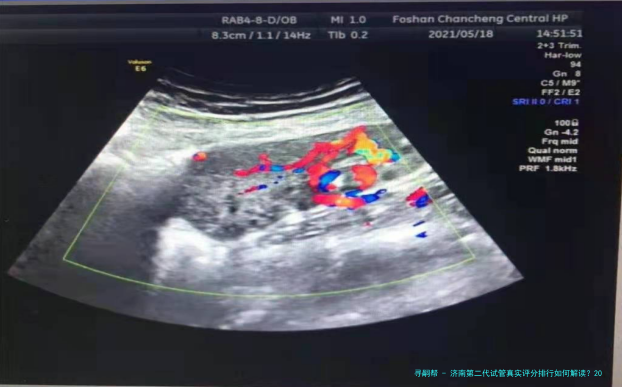

选择第二代试管(ICSI)医院时,单精子注射技术的成熟程度与胚胎培育试验室等级直接影响性价比。下列是济南地区主流医院的综合数据相比较:

时差成像意向胚胎检查筛选、卵子激活技术

取卵与单精子注射:20000-30000元(含ICSI操作费)